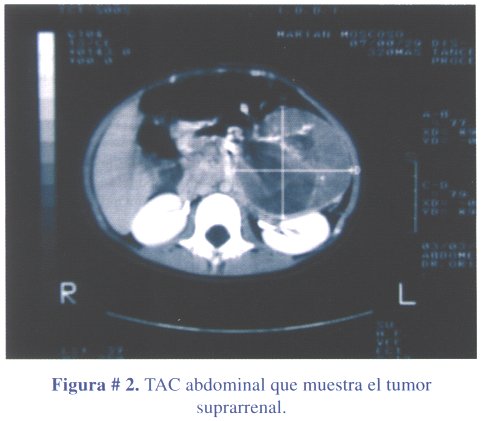

1º caso clínico: niña de 3 años y 6 meses de edad, que acudió a consulta médica por presentar dolor abdominal y vómitos a repetición, por probable trauma abdominal. La niña presentaba una masa abdominal, en flanco izquierdo, de consistencia dura, móvil, no dolorosa y vello pubiano, estadio Tanner III (figura # 1). La ecografía abdominal reportó una masa abdominal que comprimía el riñón izquierdo. La tomografía abdominal contrastada (TAC) confirmó la masa de ubicación retroperitoneal izquierda, de densidad heterogénea y que desplazaba el páncreas y comprimía el riñón izquierdo, compatible con tumor suprarrenal izquierdo (figura # 2). Los estudios de laboratorio revelaron niveles elevados de estradiol. El tratamiento fue quirúrgico, con la extirpación de la masa tumoral en su totalidad (figura # 3). El peso del tumor fue de 300 gramos.